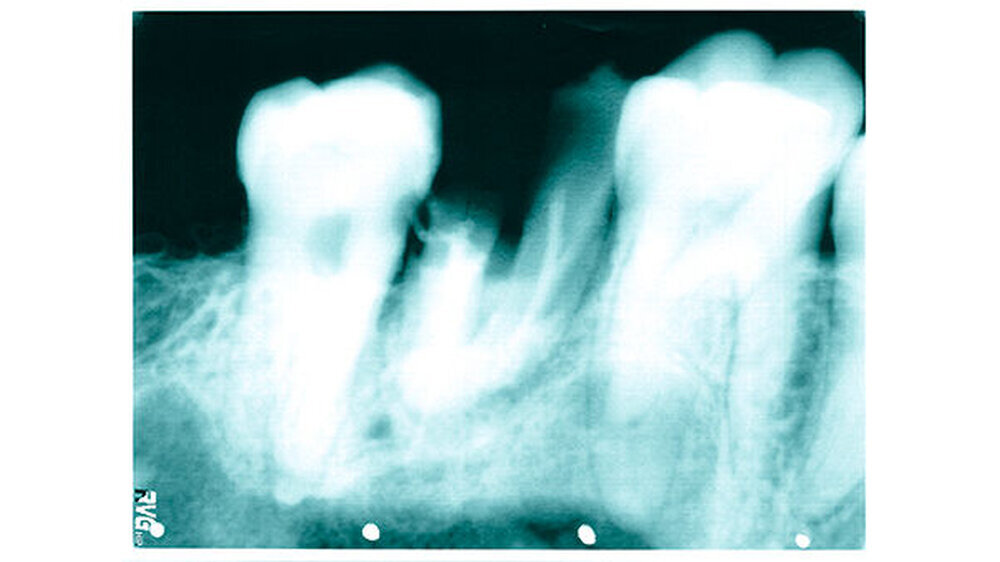

Am 14. März 2003 wurde in der Waal, bei der Gemeine Tiel (Niederlande) ein toter Mann gefunden. Er scheint aus Deutschland zu kommen. Allem Anschein nach lag die Leiche zwischen zwei bis vier Wochen im Wasser.

Das Alter des Toten wird zwischen 30 und 50 Jahren geschätzt. Er hatte schwarze Haare und trug einen Schnurrbart. Seine Größe betrug etwa 175 Zentimeter. Er trug blaue Adidas Sportschuhe in Größe 42, eine blaue Jeans der Marke EDWIN, Größe W31-L32 und dazu einen schwarzen Pullover mit Rollkragen. An seinem rechten kleinen Finger hatte er einen goldenen Trauring. Der Mann war beschnitten.